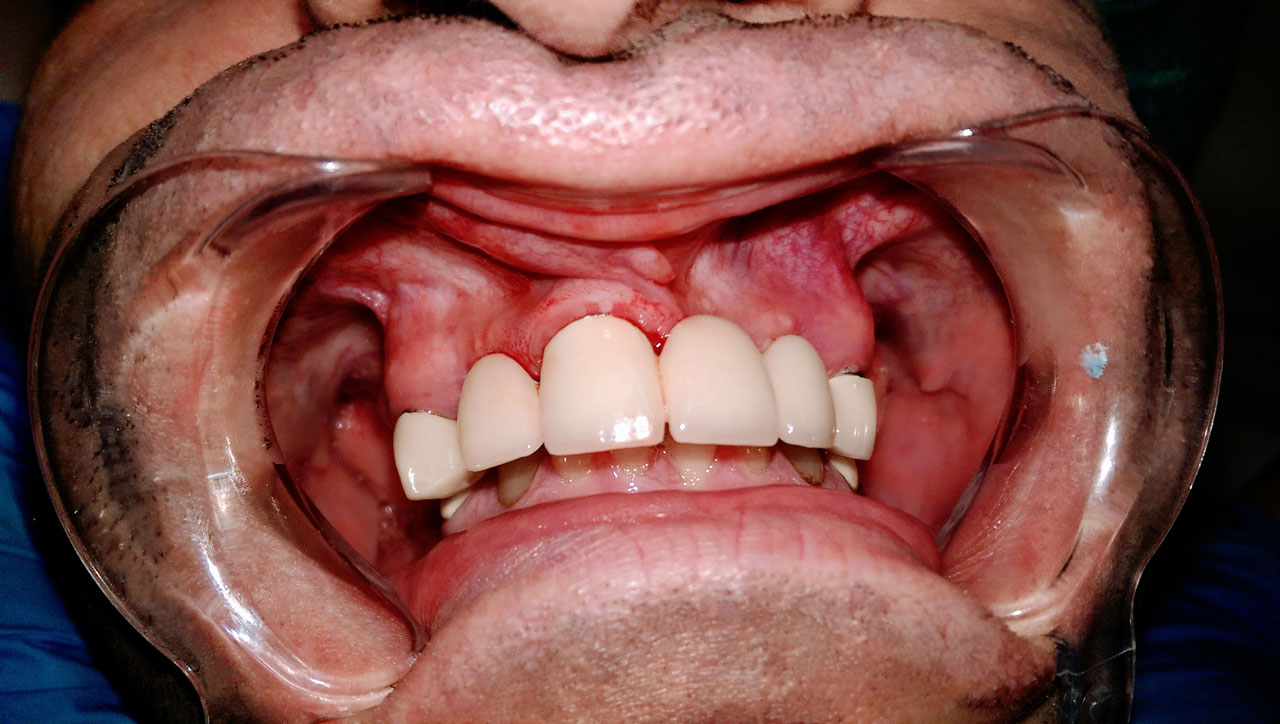

Teljes szájüregi rehabilitáció két lépésben

Ismét egy teljes szájüregi rehabilitáció két lépésben. Először az alsó fogak lettek kihúzva és azonnal implantálva, híddal ellátva, majd később a felső. IHDE svájci azonnal terhelhető implantátumok és cirkónium hidak. Dr. Kelemen Péter és a Symbion Fogtechnika közös munkája.